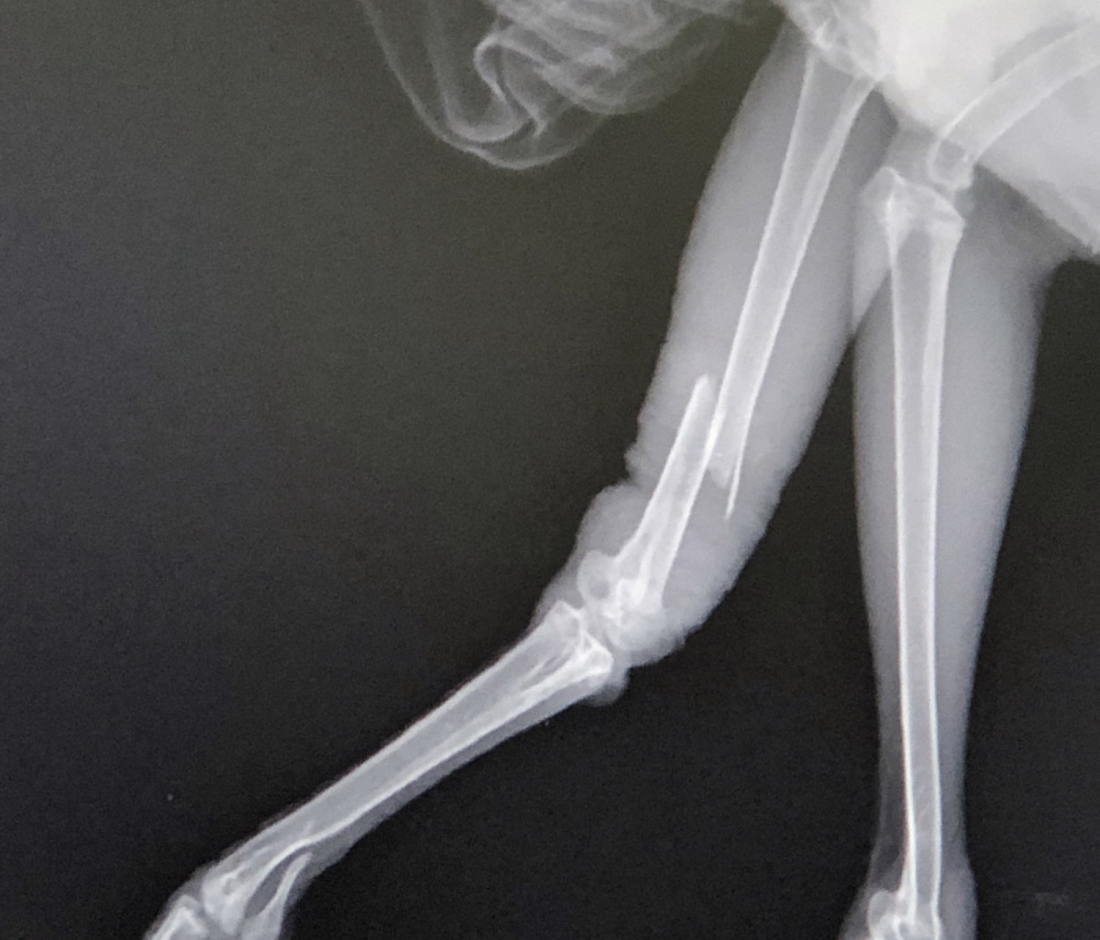

二カ月前に、巣から落ちて左脚を骨折したハシブトガラスのヒナを保護しました。翌日近くの動物病院へ連れて行くと役所へ電話するように言われ、役所で紹介して頂いた動物病院へ連れて行きました。レントゲン検査をしたら、左脚の太腿を骨折していたのでギプスをして頂き、一ヶ月間ほど一日三回、化膿止めの液体薬を飲ませました。その間二度、獣医さんに骨折した脚を牽引して正しい位置に戻し、ギプスを付け替えて頂きました。その後、ギプスによる皮膚のかぶれ等で何度か通院しました。現在は完治しています。

左脚の骨折の痕は綺麗に真っ直ぐ治ったわけではありませんが、ちゃんと左脚で体を支えて、右脚で頭をかくことが出来、普通に歩いたり着地したり出来る様になりました。数日前に通院した時の獣医さんのお話では、今後骨折あとのまわりに肉がついてくるから、極端な負荷をかけない限りは大丈夫でしょうとの事です。一ヶ月以上ギプスやテーピングをしていたので、現在 左脚の上部は羽毛がはげていますが、時期がくればちゃんと羽毛が生え揃うとの事です。

<ギプスを巻いて治療中>

<保護当時のレントゲン写真>